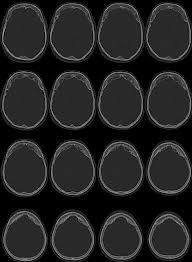

Prolapso del ventrículo de Morgagni. Inflamación crónica hiperplásica de la mucosa y submucosa del sáculo laríngeo.